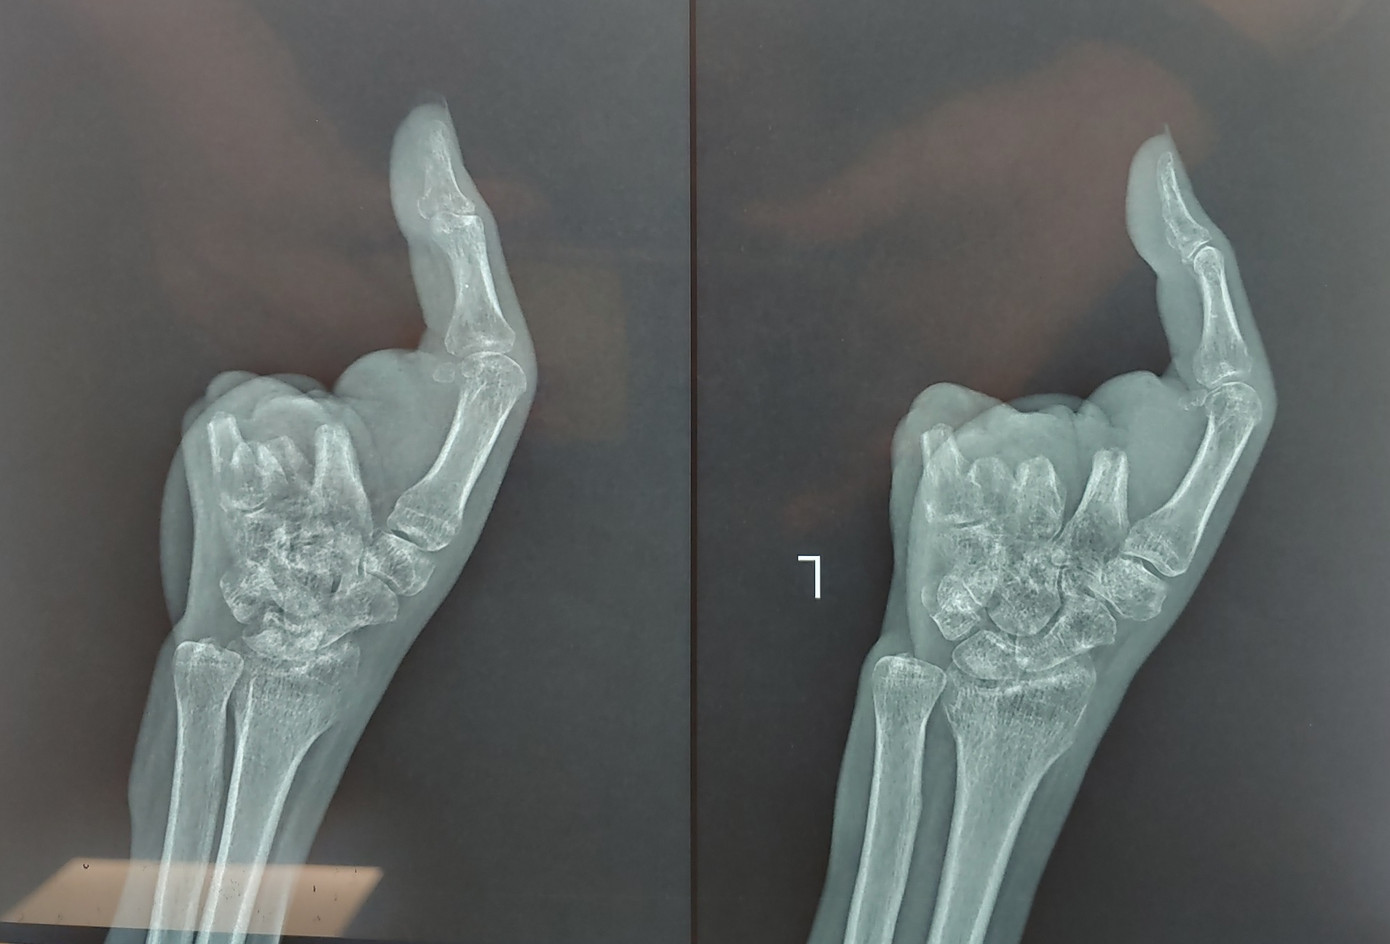

Khoảng 3 tháng trước, bệnh nhân Nguyễn Thị V (42 tuổi) trong lúc làm việc không may bị máy xay thịt cuốn bàn tay trái. Khi được giải cứu ra khỏi cối xay, bàn tay đã bị thương phức tạp, dập nát cả 4 ngón, không thể phục hồi, chỉ duy nhất còn ngón tay cái. Bác sĩ đã phẫu thuật cắt lọc vết thương dập nát, tạo mỏm cụt.

| Bàn tay bệnh nhân bị cụt mất 4 ngón sau khi bị máy xay thịt cuốn nát |